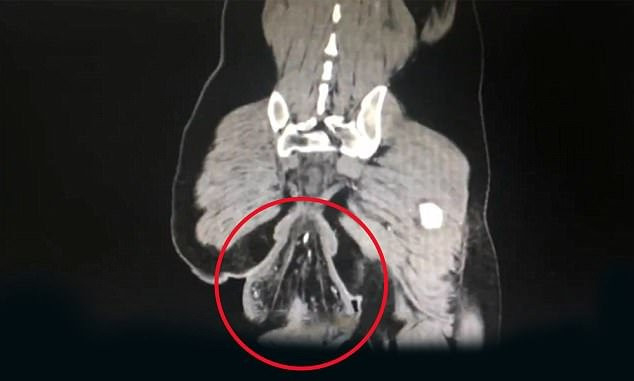

Các bác sĩ cho biết, dị vật lòi ra ngoài hậu môn là trực tràng và nó đã mất sự gắn bó với cơ thể của mình, theo các báo cáo từ Trung Quốc.

Dị vật lòi ra ngoài hậu môn của người đàn ông Trung Quốc là trực tràng.

Các chuyên gia cho biết tình trạng này là sa trực tràng – căn bệnh xảy ra do phần cuối của ruột già mất sự gắn kết với cơ thể và lòi ra bên ngoài hậu môn. Các bác sĩ cho biết, căn bệnh xảy ra do người đàn ông ngồi hơn 30 phút trong nhà vệ sinh. Bệnh nhân này cũng thừa nhận mình chơi game trên điện thoại di động khi đang đi vệ sinh.

Bác sĩ Su Dan, điều trị tại khoa phẫu thuật dạ dày – ruột của Bênh viện thuộc Trường ĐH Sun Yat Sen, cho biết: "Bệnh nhân bị sa trực tràng từ khi lên 4 tuổi nhưng phần trực tràng lòi ra ngoài có thể tự thu lại. Tuy nhiên, bệnh nhân đã không đủ điều kiện để điều trị khi đó nên khiến tình trạng trở nên tồi tệ hơn".

Sa trực tràng thường xảy ra ở trẻ em và người cao tuổi. Ở một số trẻ em, bệnh là do rối loạn chức năng bẩm sinh. Tuy nhiên, trong trường hợp của nam bệnh nhân trên, nguyên nhân chính khiến trực tràng bị tuột ra ngoài là do đi vệ sinh quá lâu. Tư thế ngồi hay ngồi xổm khi đi toilet sẽ gây áp lực lên khoang bụng. Nếu các cơ trong vùng chậu bị yếu thì áp lực đó sẽ đẩy trực trạng ra ngoài qua lỗ hậu môn, các bác sĩ cho biết.